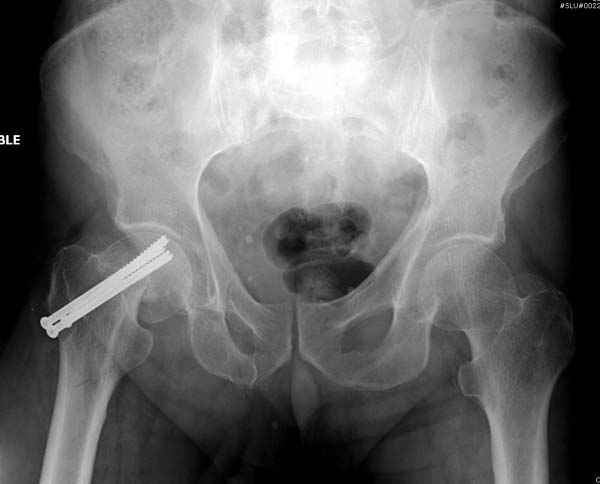

На второй день после выписки упал дома. Снимки приложены. Коллеги рекомендуют удаление шурупа и вытяжение. Что делать?

"Решайте проблемы по мере поступления. На первом этапе решение одно, и на мой взгляд верное. Ситуация изменилась кардинально - другое решение. Я бы избрал ресинтез, убрав винты заменил на Гамму. Что с ним будет послезавтра? - Будем решать послезавтра. Такая наша доля."

Правильно, ситуация изменилась, как говорят у нас теперь "different animal", надо решать проблему подвертельного перелома. При наличии различных вариантов фиксаторов, включая Страйкер Гамма 3, мы выбрали DePuy Antegrade Trachanteric Nail из-за многовариантности проксимальной фиксации и двойного изгиба. Вводится через вертел под 8 градусным углом, и есть достаточный передний диафизарный изгиб, предупреждающий пенетрацию дистального переднего кортекса.

Кто знает что дальше, мысленно готовы к проксимальной артропластике.

Но ведь и головка бедра сползла в варус - отчего ограничились только фиксацией подвертельного перелома, а не убрали винты и не сделали репозицию шейки?